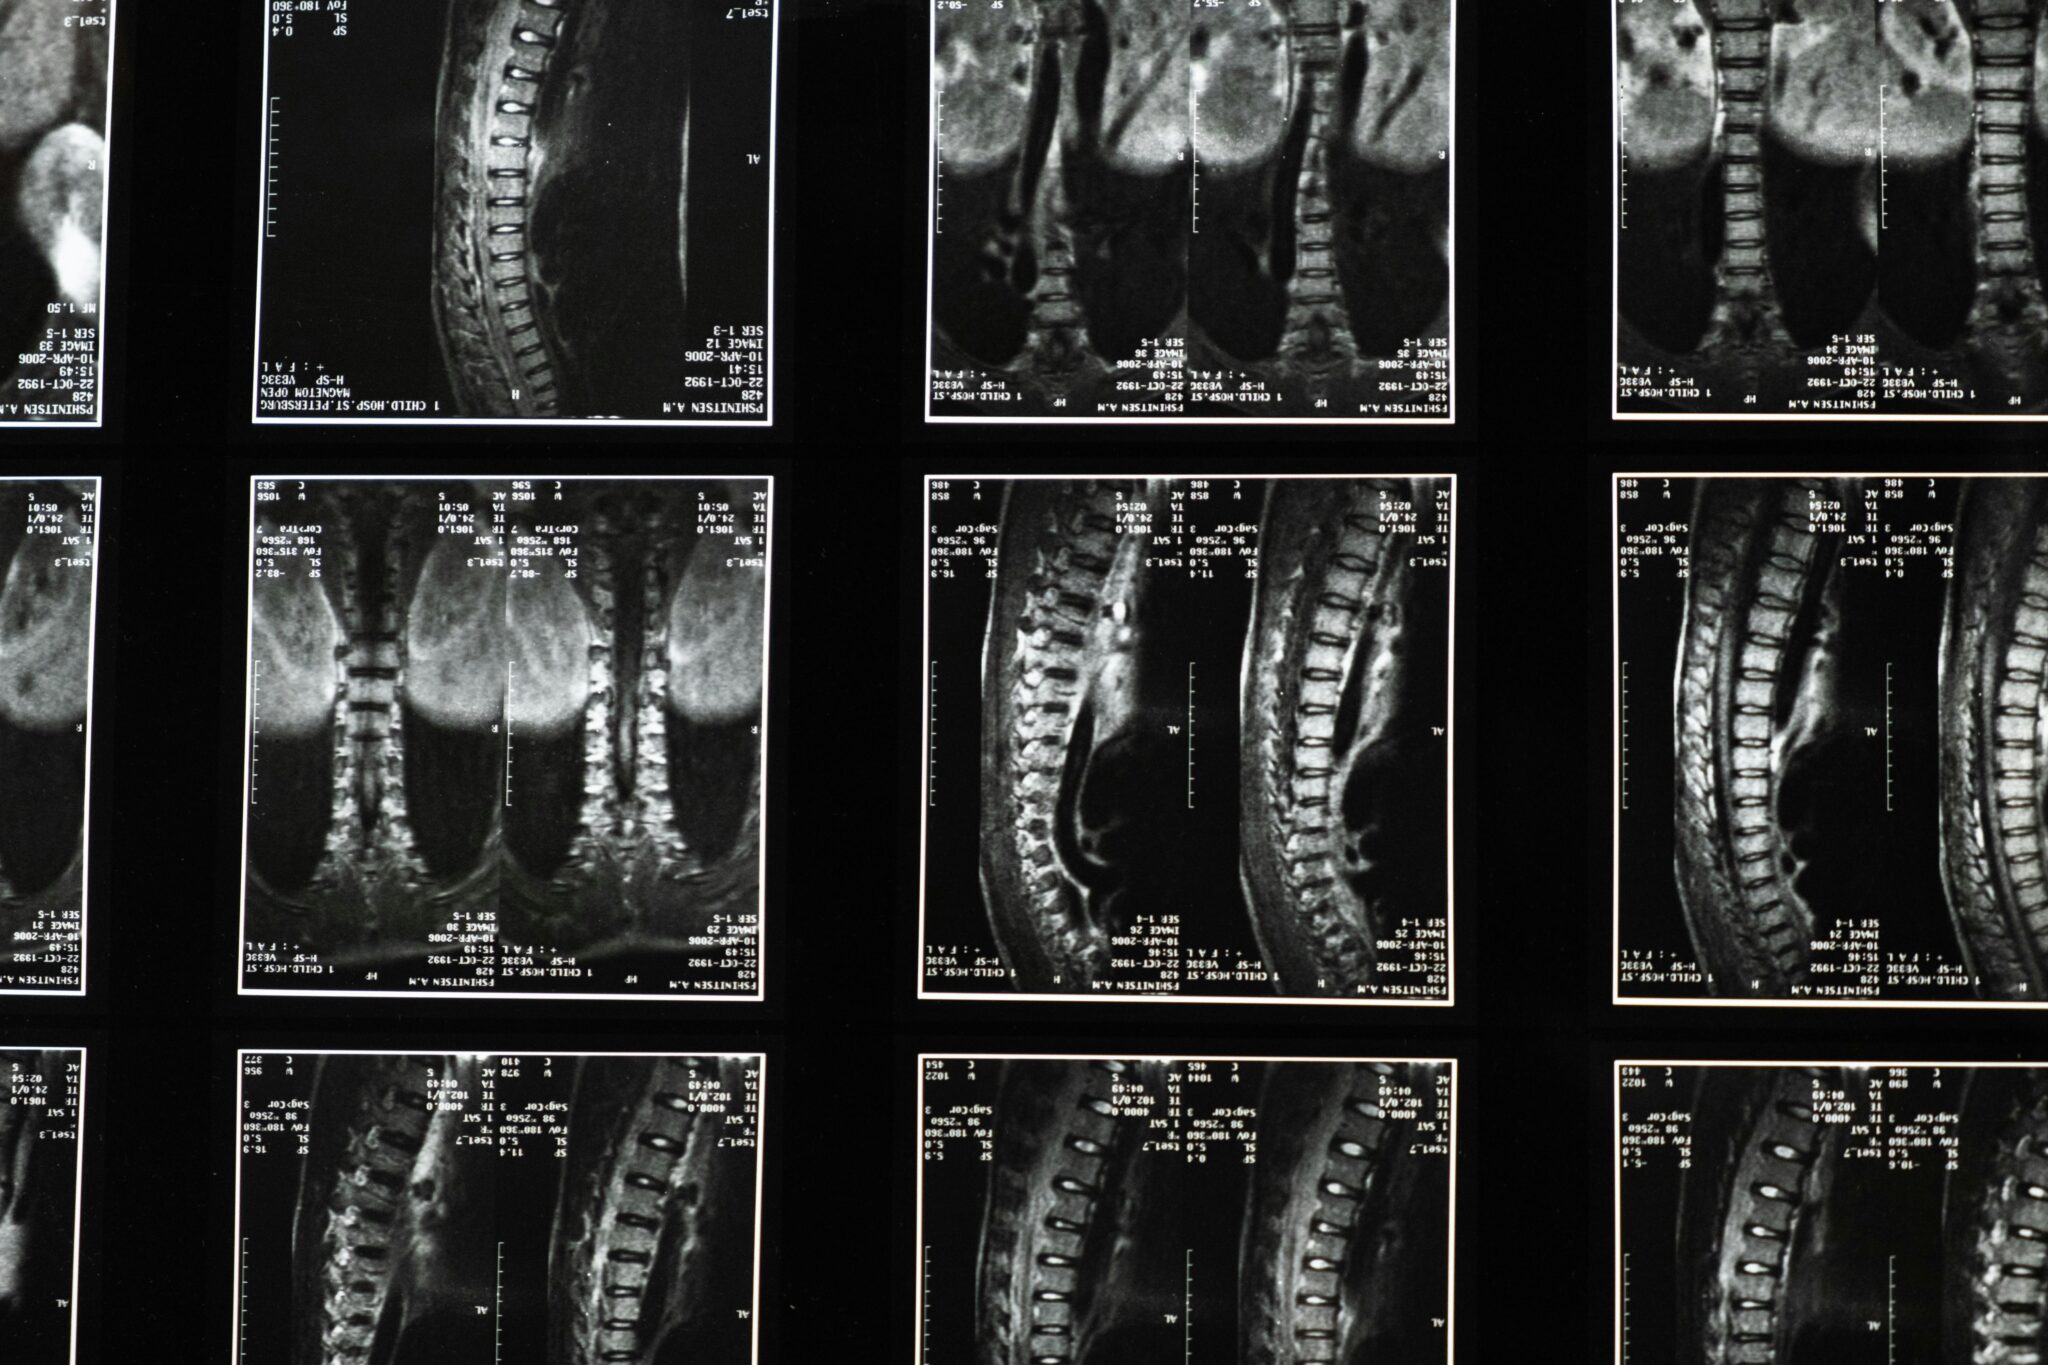

Medical Imaging and Specialist Evaluation: Why They Matter

Back and spine injuries aren’t always visible immediately. X-rays can miss disc injuries and soft tissue damage. MRIs often provide the clearest picture of disc herniations, nerve compression, and spinal cord issues. CT scans may be critical for fractures.

Specialist evaluation—neurology, orthopedics, neurosurgery—can also strengthen the clarity of diagnosis and treatment needs. Insurance companies often respect specialist documentation more than vague notes from early urgent care visits.